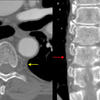

AE interface a)

AE interface b)